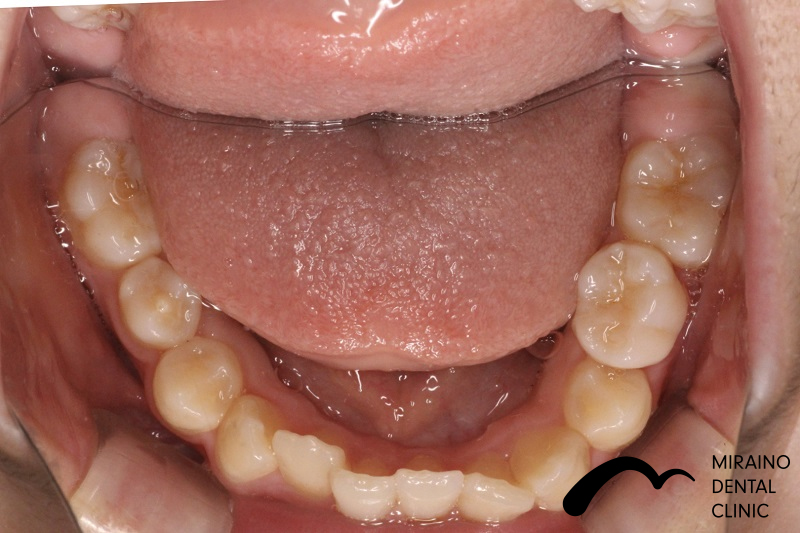

過蓋咬合②

| 施術名 | マウスピース矯正(インビザライン) |

| 施術の内容 | 歯科矯正でも目立ちにくい新しい矯正方法です。 透明に近いマウスピース型の矯正装置(アライナー)のため、歯に装着しても目立つことなく歯並びを矯正することが出来ます。 また、一人ひとりの合わせて矯正装置を作製いたします |

| 治療費 | インビザライン990,000円 |

| 考えられるリスク、副作用 | 疼痛・咬合時痛を生じる事があります。 時間経過とともに治ります。 |

| 考えられるリスク、副作用[矯正] | 継続使用により緩んだり、外れやすくなる事があります。 割れたり壊れたりする事があります。 諸々の事情により、治療期間が当初よりも伸びる事があります。 所定の装着時間22時間を守って頂けない場合、治療計画どおりに治らない可能性があります。 歯が動く際に、痛みが出る事があります。 矯正期間中は虫歯や歯周病のリスクが高まりますので、しっかりとしたケアが必要です。 歯の移動に伴う歯肉退縮や歯根吸収が起こる事があります。 インビザライン・システム(invisalignR)は、アメリカのアラインテクノロジー社より提供されている、カスタムメイドの矯正装置ならびに、これを用いた治療システムを指します。 インビザラインを用いた治療は保険適用外の自由診療となります。 厚労省の認可(医薬品医療機器等法上の承認)は得ていないため、まだ明らかになっていないリスクが存在する可能性があることをご了承ください。 |

| 全て | 必ずしもご希望通りの見た目にならない事があります。 |